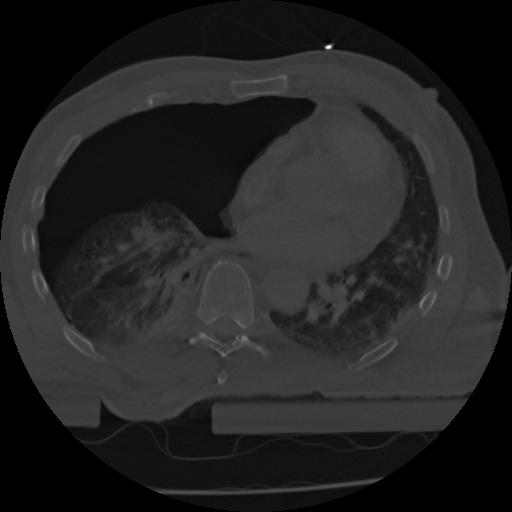

22 ANGIO,CE,Vol,0.5,ANGIO,,